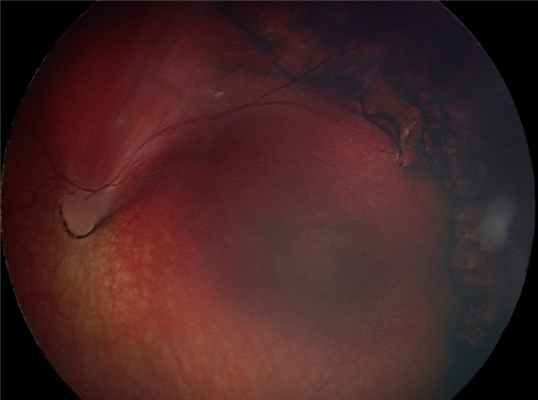

Глазное дно ребёнка А. до операции.

Глазное дно ребёнка А. после операции.